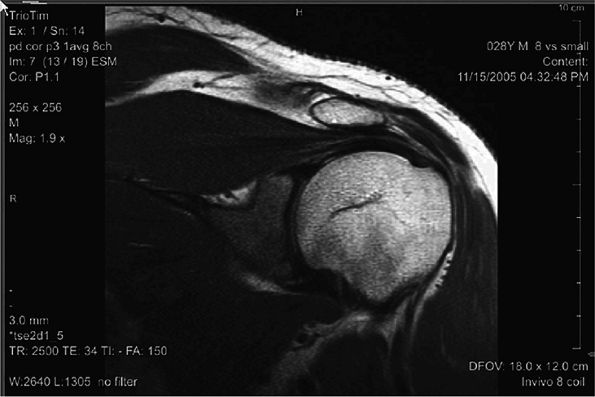

|

FIGURE 2.6 ● Image of the shoulder acquired at 3T using an eight-channel shoulder array. Slice thickness is 3 mm with 0.47 × 0.47 mm in-plane resolution.